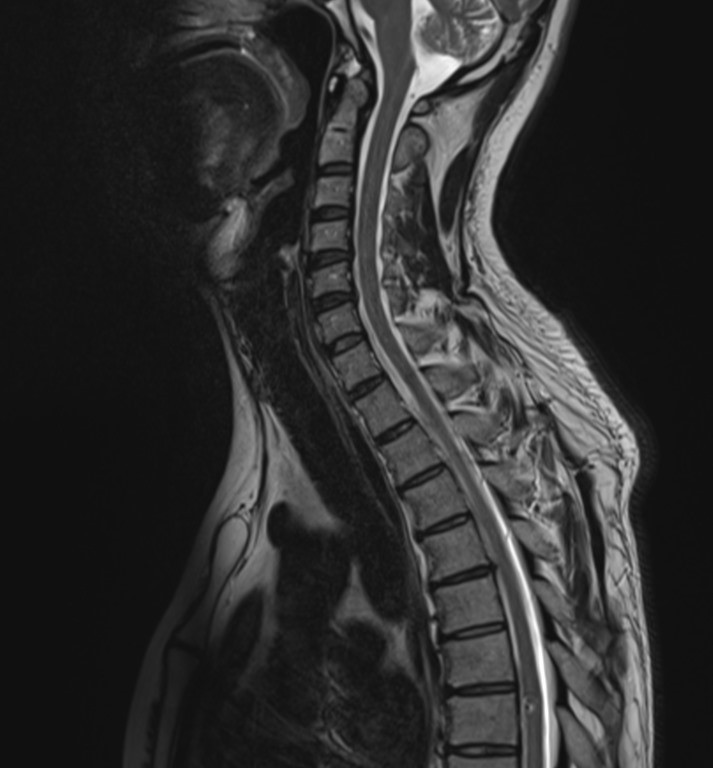

Resonancia Magnética de Columna

Envíado por Dr. José Rafael Chang Calero